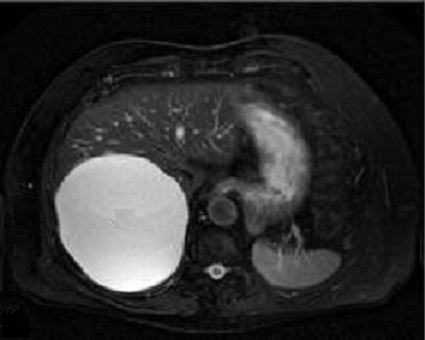

intraveineuse . Aspect IRM est une formation lesionaire

hyperintense T2 et hyposignal en T1 ; apres imjection ne se

rehausse pas .

Aspect

radiologique d'une kyste biliaire simple du foie

.Lesion est tres hyperintense en T2 |

Et est hyposignal en T1 . N'a pas de

rehaussement apres injection de contrast

intraveineuse . Image TDM en coupe axiale . |